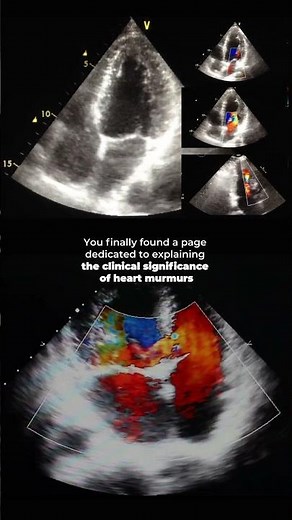

Ultrasound - Heart Murmur

On Echo - Baby Heart Murmur

Echocardiogram - Real